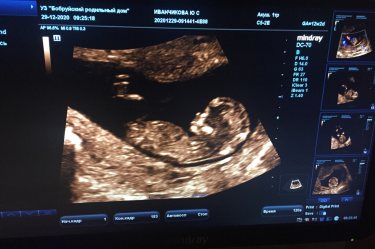

Ну вот и мой пузожитель) срок 12 нед и 2 дня. Сегодня была на первом скрининге, по узи все хорошо) слышала сердечко... это такое непередаваемое ощущение...